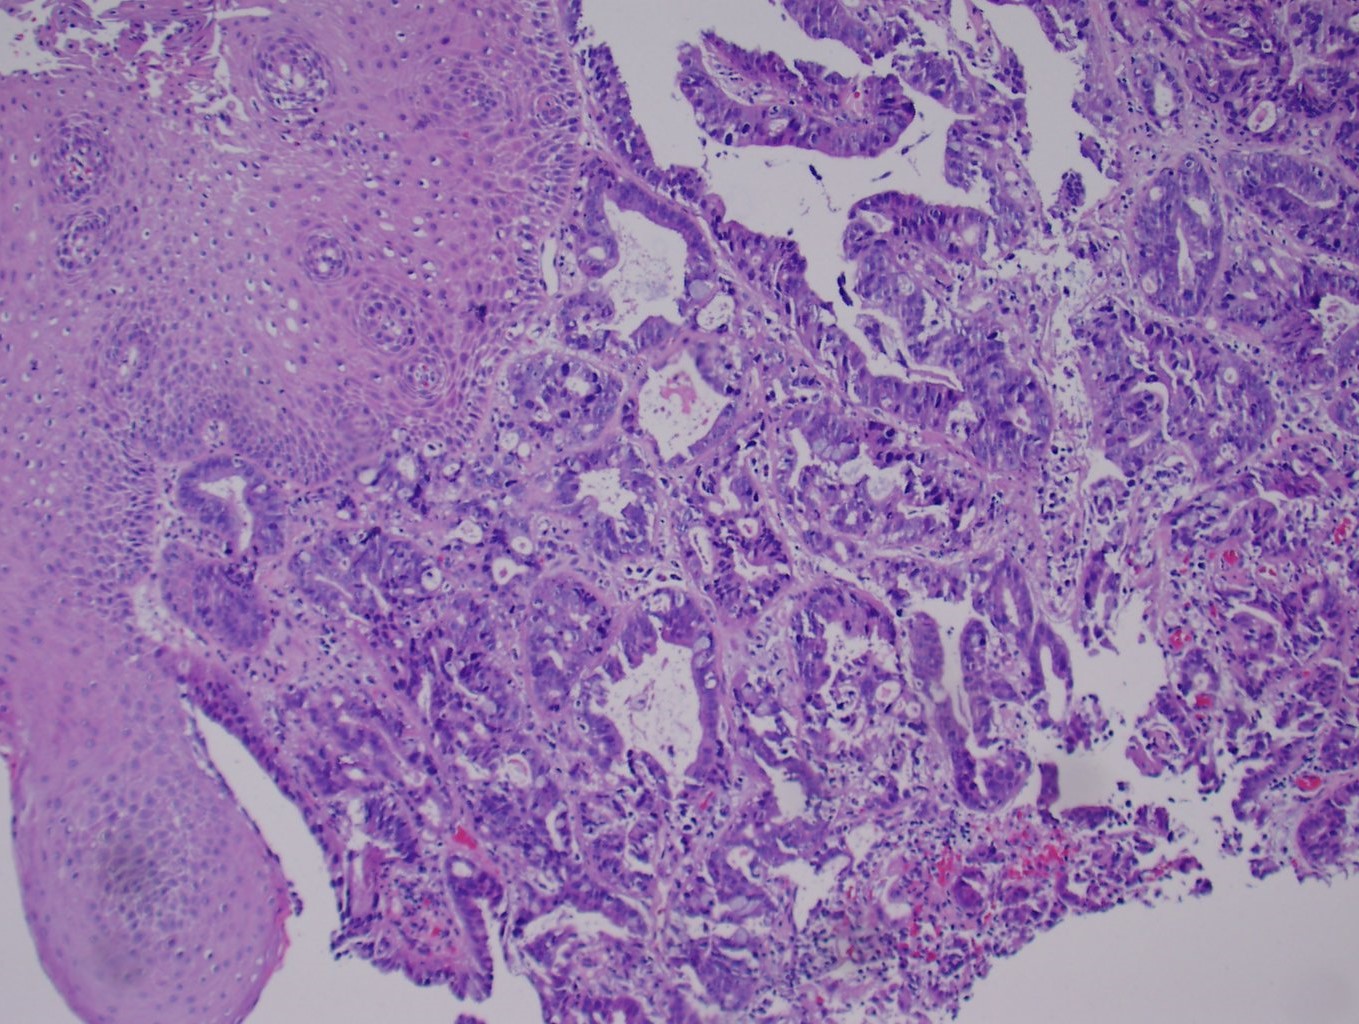

Беременность децидуит

Беременность децидуит 114 фотографий